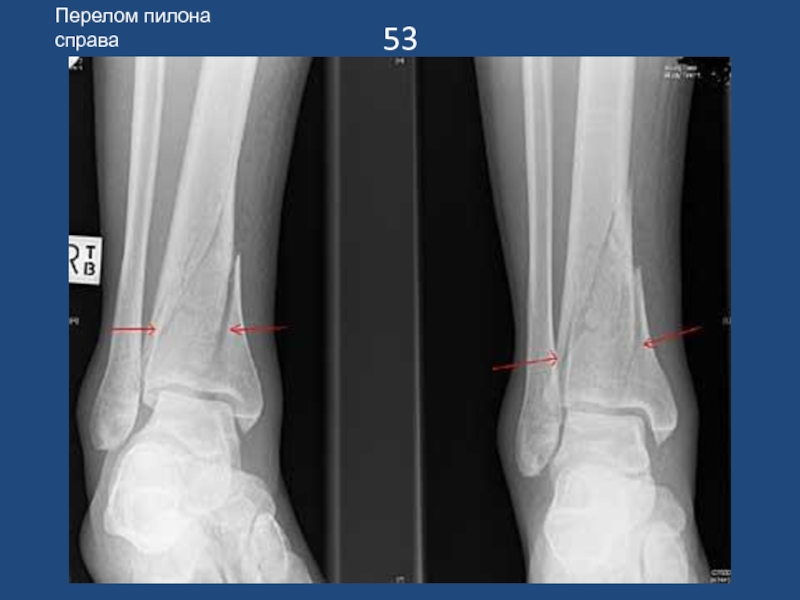

Слайд 5453

Перелом пилона справа

53Перелом пилона справа